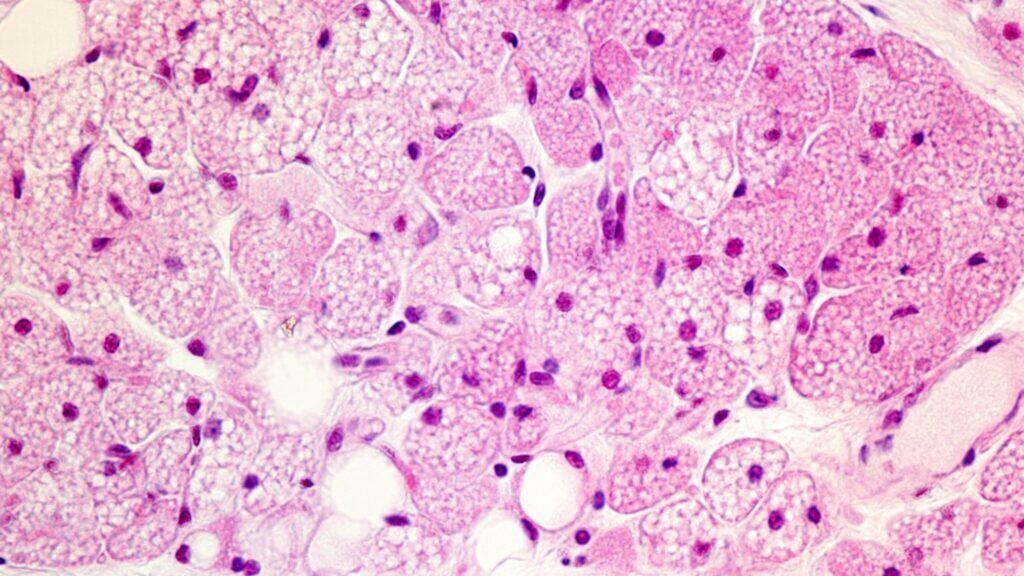

Para entender seu papel com mais profundidade, os cientistas removeram a proteína do organismo de camundongos. O resultado foi surpreendente: os animais não se tornaram obesos; ao contrário, desenvolveram lipodistrofia, condição marcada pela perda grave de gordura corporal. Essa alteração levou a riscos metabólicos semelhantes aos observados na obesidade, como resistência à insulina, inflamação e acúmulo de gordura em órgãos internos.

Esses achados reforçam que não é apenas a quantidade de gordura no corpo que importa, mas a qualidade e funcionalidade dos adipócitos. Quando as células de gordura não conseguem desempenhar suas funções regulatórias, tanto a deficiência quanto o excesso podem gerar consequências graves.